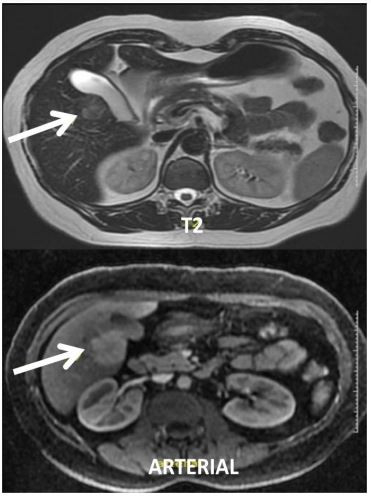

Paciente com antecedente de hepatopatia por vírus da hepatite C, tratado em 2017. Apresenta carga viral negativa. Em acompanhamento ambulatorial, ultrassonografia de abdome demonstra lesão em periferia de segmento V e endoscopia digestiva alta sem sinais de hipertensão portal. Exames laboratoriais: Hb= 12,3g/dL; Leucócitos= 3.500mm³ ; Plaquetas= 236.000mm³ ; Bilirrubina Total= 0,89mg/dL; Albumina= 4,8g/dL; RNI= 1,21; Na= 145mEq/L; Creatinina= 0,87mg/dL; Alfa fetoproteína= 1,4 mg/dL (MELD= 9) Realizou ressonância magnética com gadolíneo:

Mediante aos achados descritos, a hipótese diagnóstica e a conduta são: